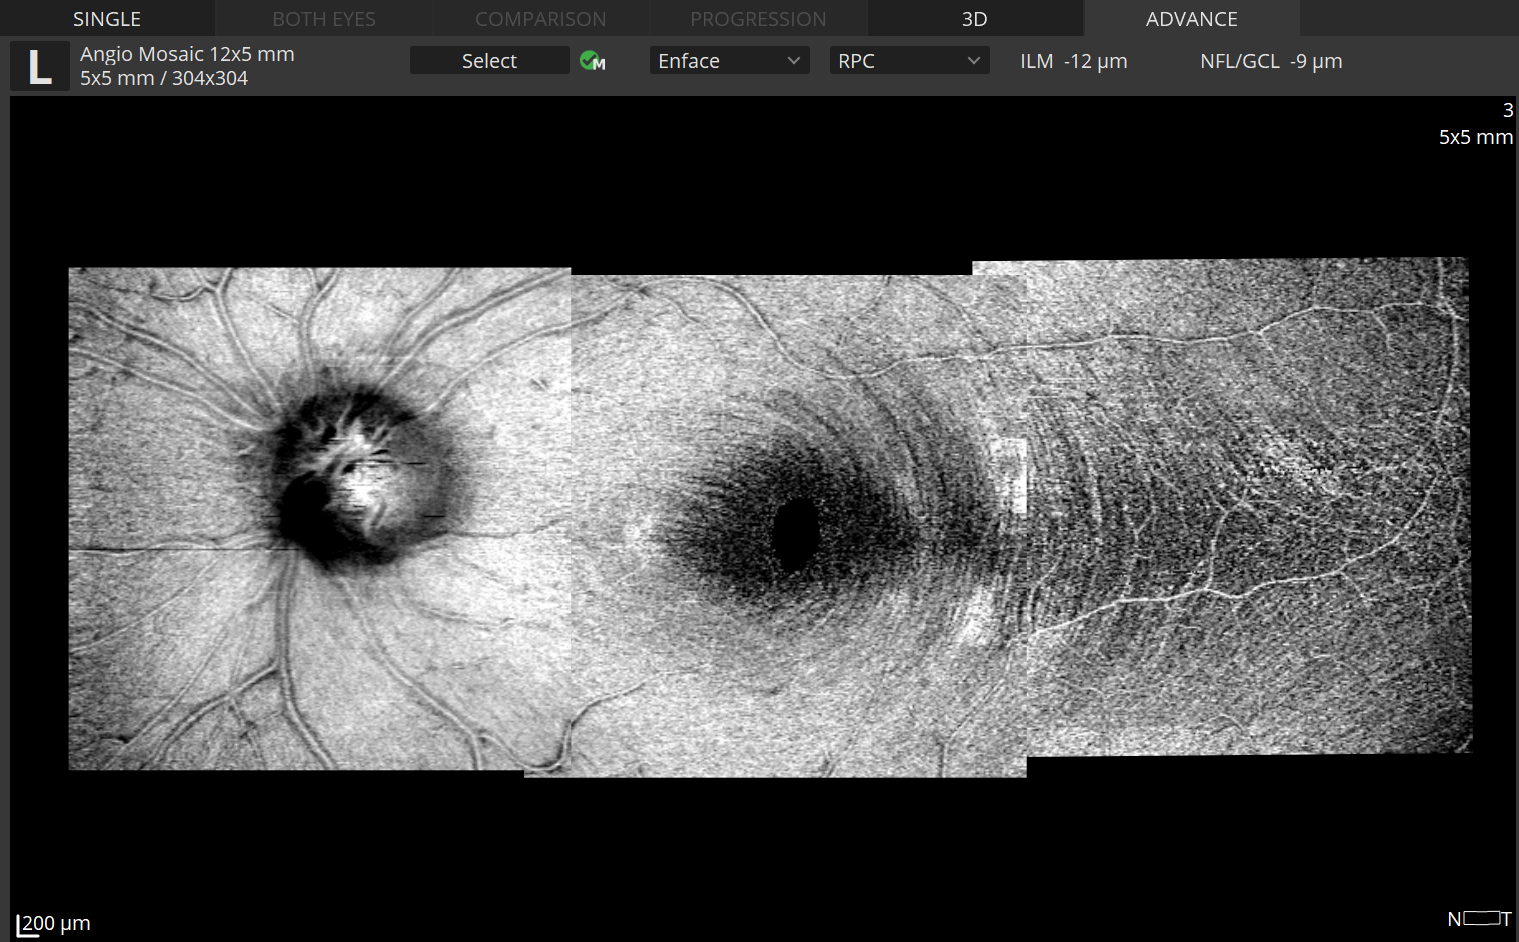

OCT-A Mosaic

The Angiography mosaic delivers high-detailed images over large field of the retina.

Advanced tab:

provides view of any vascular layers, enface view of vascular layers, depth coded and thickness map.

Mosaic modes:

10×6 mm, 12×5 mm, 7×7 mm, 10×10 mm and Manual (up to 12 images).

Manual mode:

allows to scan the desired region.Built-in analytics allow to see vascular layers, enface or thick-ness maps.